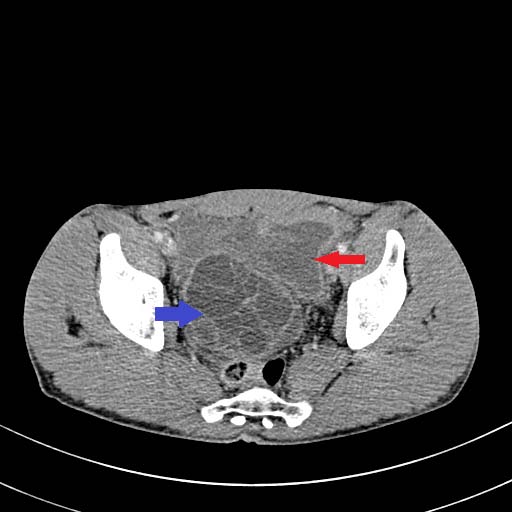

Une tomodensitométrie abdomino-pelvienne est réalisée sans et après injection de produit de contraste. Cette dernière, montre au niveau du foie droit Corresponding Author ?: Internat Hôpital Ibn Sina 40010 Rabat, Maroc. e-mail: [email protected] de multiples formations kystiques, à contenu liquidien pur ou cloisonné, bien circonscrites, confluentes, à paroi épaissie rehaussées en périphérie après injection de produit de contraste en rapport avec des kystes hydatiques hépatiques de taille et de type variable.

Il s'y associe également au niveau pelvien deux kystes hydatiques intra-péritonéaux, le premier est multi vésiculaire et le deuxième sus et latéro-vésicale gauche à paroi affaissée, discontinue associée à un épanchement péritonéal témoignant sa rupture dans la cavité péritonéale.

Le diagnostic de péritonite aigue généralisée par rupture d'un kyste hydatique intra-péritonéal associée à une hydatidose hépatique est retenu.